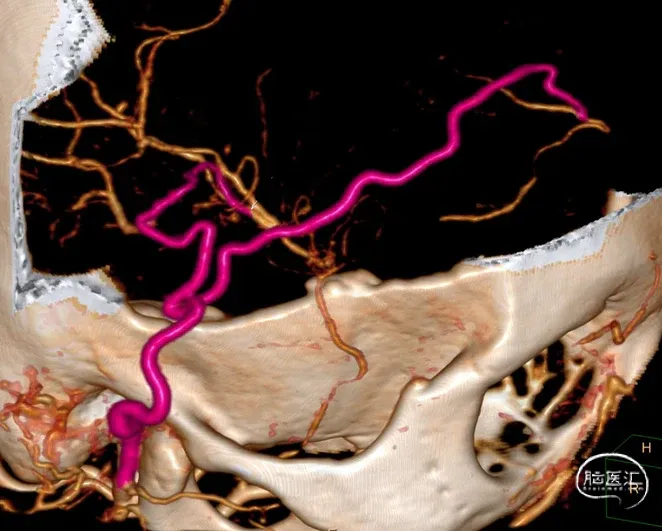

图4 术后2个月头部影像学检查所见:上图,CTA显示,右颞浅动脉与大脑前动脉、右颞浅动脉与大脑中动脉吻合口通畅;

中图1,中图2,右颈外动脉正位和侧位DSA显示,右颞浅动脉与大脑前动脉、右颞浅动脉与大脑中动脉吻合口通畅;

下图,右颈总动脉正位DSA显示,右大脑中动脉M1段烟雾样血管减少。【18】